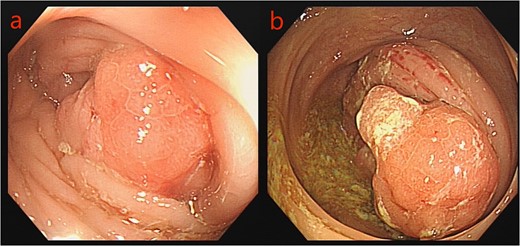

Given the patient’s unsuitability for immediate radical surgical resection, the patient was administered monotherapy with capecitabine to control tumor progression. During an outpatient follow-up, a slight enlargement of the tumor was observed in the ascending colon region. To further understand the patient’s condition, he was readmitted to the hospital, to undergo laboratory tests, serum CEA: 26.10 ng/ml, uric acid: 447 umol/L, and platelet levels were normal. Repeated enhanced CT scanning of the abdomen revealed complete recovery from the obstruction (Fig. 3). To ascertain the nature of the ascending colon tumor,a repeat colonoscopy examination through colostomy showed the sigmoid and ascending colon tumor. The biopsy of the ascending colon tumor revealed an adenocarcinoma (Fig. 4). Given the patient’s concomitant small B-cell lymphoma and primary thrombocytopenia, surgical treatment was decided after a multi-disciplinary team discussion.

Colonoscopy images: a: sigmoid tumor; b: ascending colon tumor.